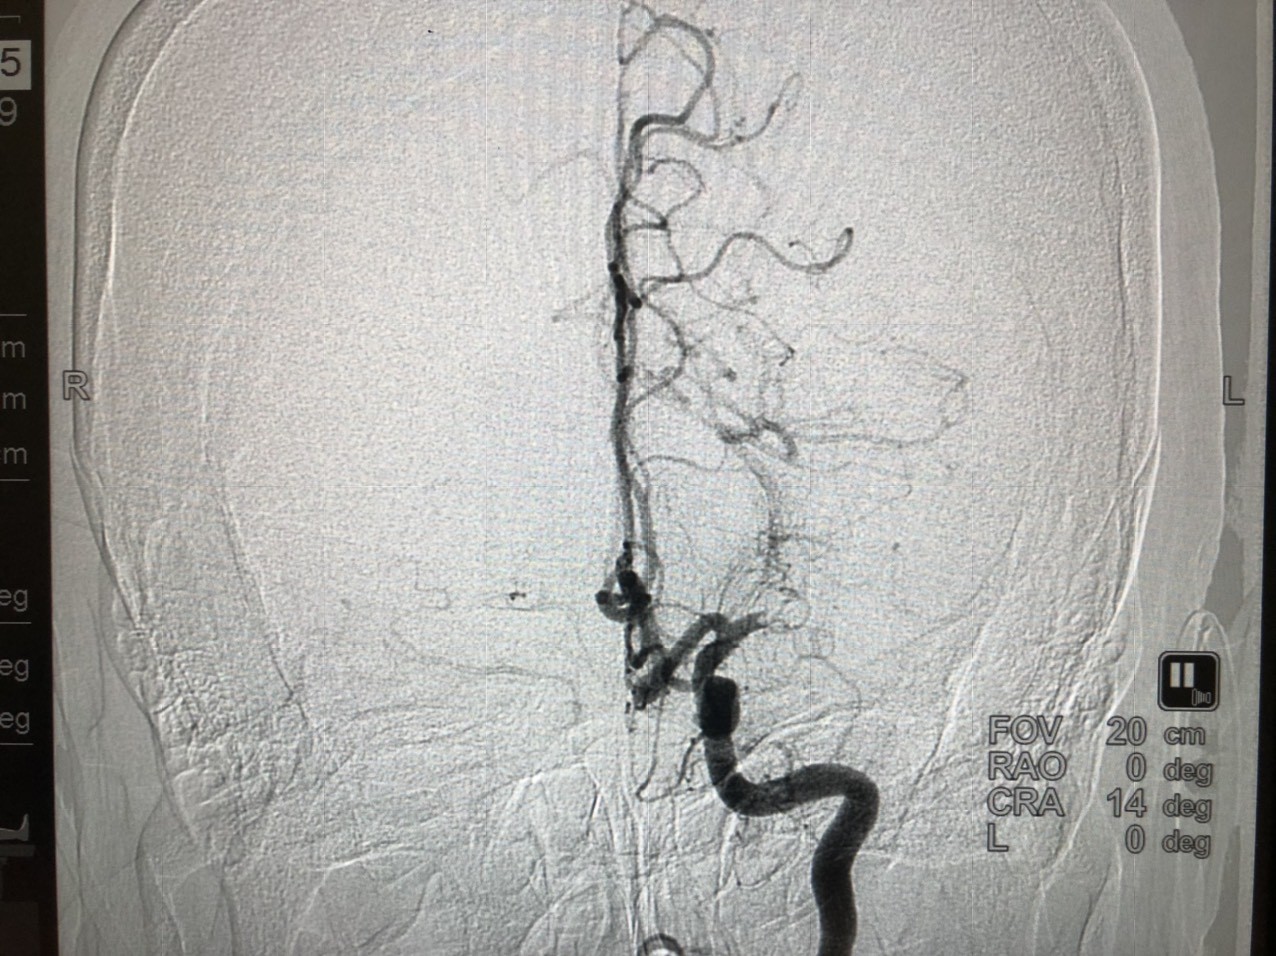

![]() |

| Hình ảnh tắc mạch máu não được chụp trên hệ thống chấn đoán hình ảnh DSA cao cấp của BV Vinmec Đà Nẵng |